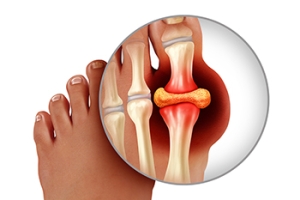

Causes and Relief From Toe Arthritis

Toe arthritis is a condition where the joints in the toes become inflamed, causing pain and stiffness. The most common cause is osteoarthritis, which occurs as the cartilage in the toe joints wears down over time, often due to age or repetitive stress. Other causes include rheumatoid arthritis or injury to the toe. Symptoms of toe arthritis include pain in the affected joint, particularly during movement, swelling, and a reduced range of motion. In some cases, the joint may become deformed or misaligned. Relief from toe arthritis involves wearing proper footwear that provides support and cushioning, as well as anti-inflammatory medications to reduce pain and swelling. Specific exercises can also help improve joint flexibility and strength. In severe cases, surgical options may be considered to restore function and alleviate pain. If you have symptoms of arthritis in your toes, it is suggested that you consult a podiatrist who can offer you effective relief and management tips.

Arthritis is a joint disorder that involves the inflammation of different joints in your body, such as those in your feet. Arthritis is often caused by a degenerative joint disease and causes mild to severe pain in all affected areas. In addition to this, swelling and stiffness in the affected joints can also be a common symptom of arthritis.